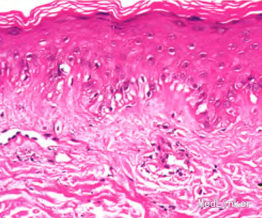

体格检查:系统检查未见明显异常。皮肤科检查:额面部、头皮、躯干及双上肢泛发环状紫红斑和斑块,覆粘着性鳞屑,部分中央结痂、萎缩。实验室检查:血常规中白细胞2.09,红细胞3.15,血红蛋白98 g。尿常规中尿蛋白(+/一)(后多次复查,尿蛋白均为阴性)。(ENA)全套检查示:抗核抗体(ANA)1:320,斑点型,抗心磷脂抗体58.4RU/mL(<12.0 RU/mL),抗ss—A抗体弱阳性,抗组蛋白抗体弱阳性。皮损组织病理检查:表皮萎缩,基底细胞液化变性,可见胶样小体,基膜增厚,真皮浅层有少量游离色素和噬色素细胞,血管周围有稀疏的慢性炎性细胞浸润。